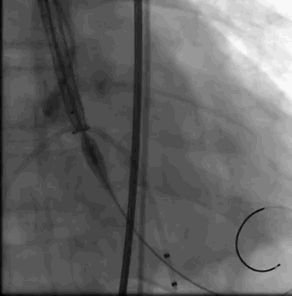

术中影像

主动脉根部造影

导丝跨瓣

选择BaIt23球囊进行预扩